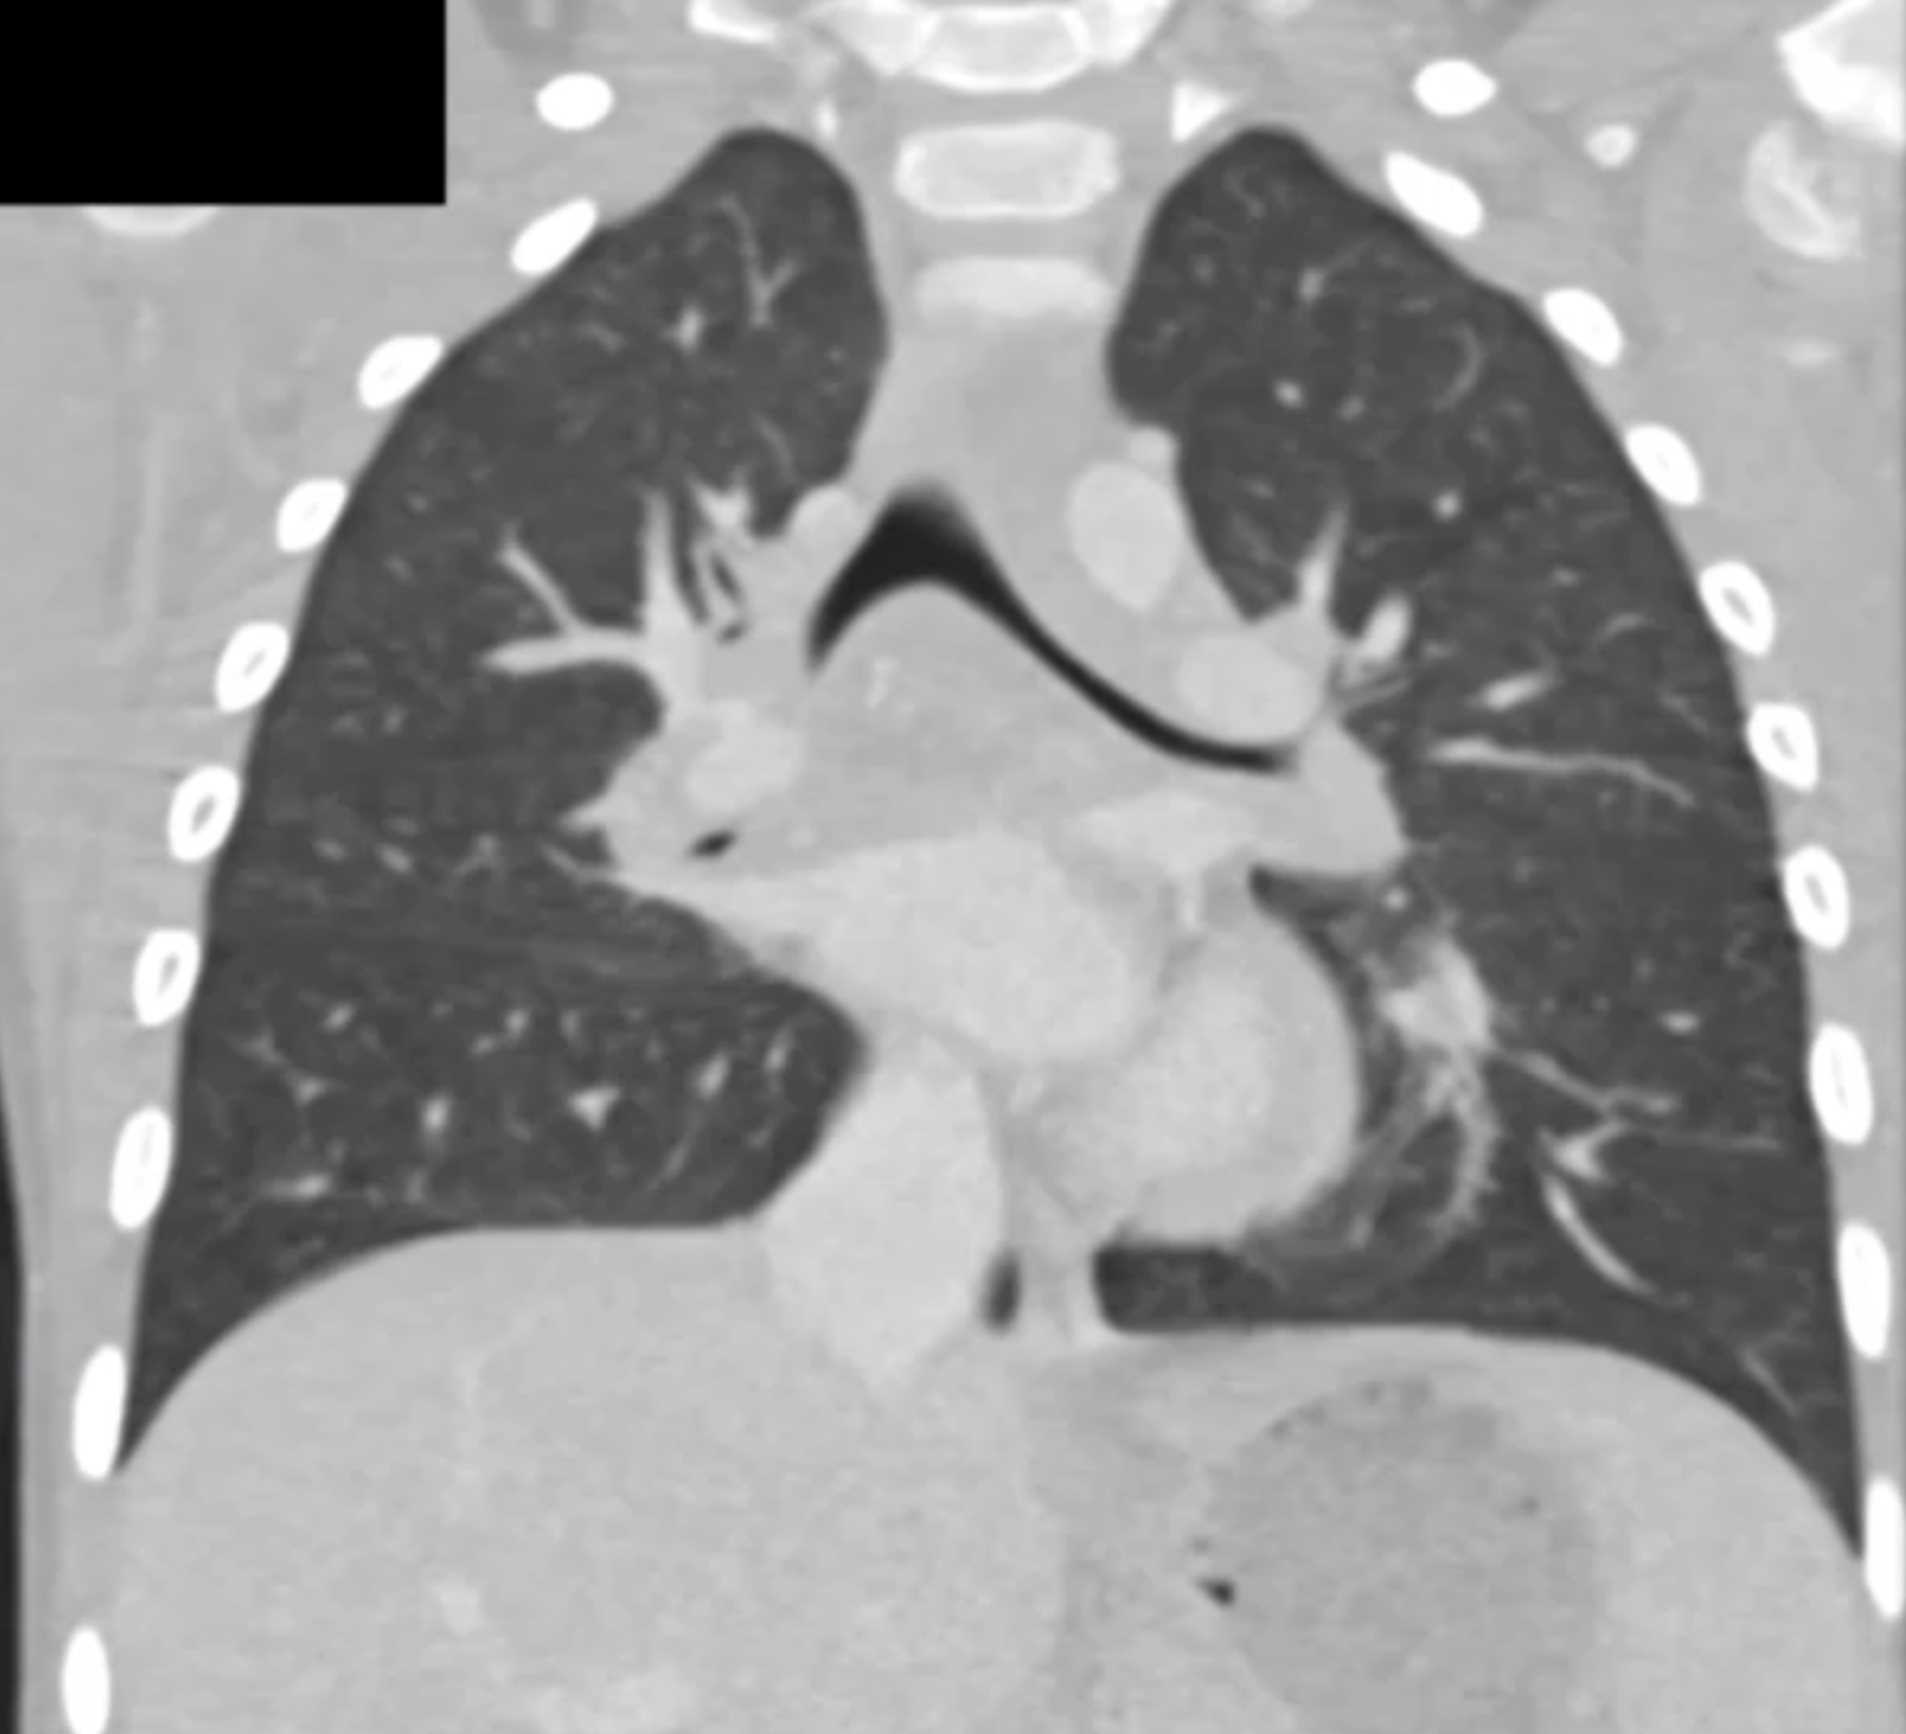

Histoplasmosis and Normal Thymus